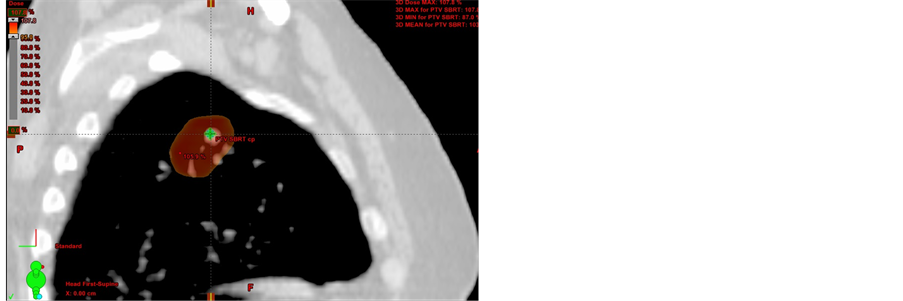

Data from thirty-nine patients who underwent SBRT lung treatment were used for this study (Figure 3(a), Figure 3(b)).

Their prescribed doses were either 5 daily fractions of 10 Gy or 4 daily fractions of 12.5 Gy, for a total dose of 50 Gy using SBRT. The patient characteristics are summarized in Table 1.

Figure 3. A 70-year-old woman with lung cancer was treated with SBRT for a total dose of 50 Gy given in 5 fractions.